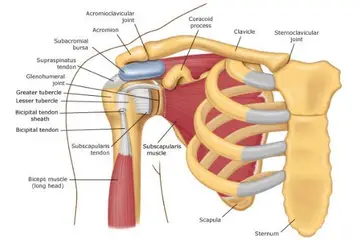

- Hareket kısıtlılığı: Kemiklerin sağlığı bozulduğunda, eklem hareketliliğinde azalma yaşanabilir. Bu, günlük yaşam aktivitelerini etkileyebilir.

- Fizik tedavi: Egzersiz programları ve fizik tedavi, hareket kabiliyetini artırmak ve kas gücünü desteklemek amacıyla uygulanabilir.

- Cerrahi müdahale: Gerekli durumlarda, kemik onarımları veya eklem değişimi gibi cerrahi işlemler düşünülebilir.